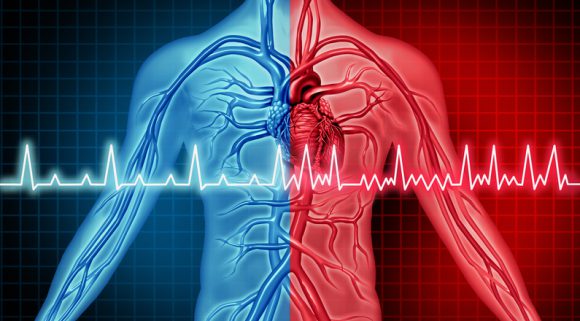

심방세동(A-Fib)은 심장이 불규칙하게 빨리 뛰는 증상으로 부정맥의 일종이다. 심부전은 심장의 기능이 떨어져 혈액을 몸에 제대로 공급하지 못해 생기는 질환이다.